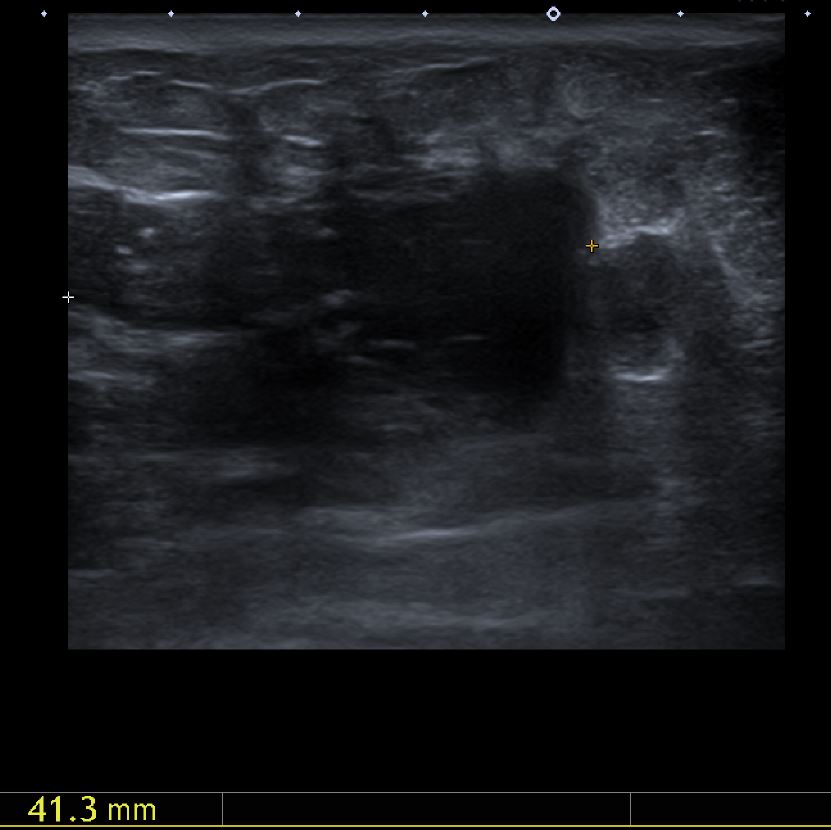

좌측 유방에 만져지는 몽우리로 내원하신 50대 여성분으로 본원에서 중심 핵 생검 시행

하여 좌측 침윤성 유관암 진단 되었습니다.